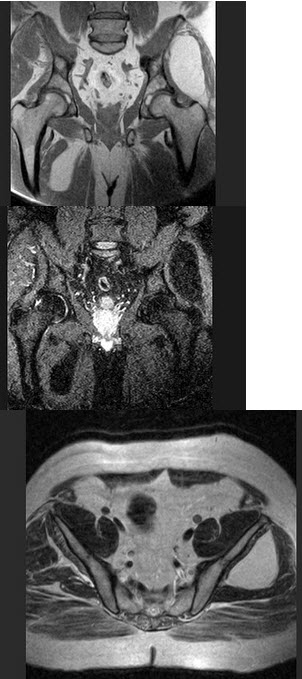

女,28岁,臀部痛,结合图像,最可能的诊断是( )

A:肌内脂肪瘤

B:肌内脓肿

C:出血

D:骨样骨瘤

E:血管瘤